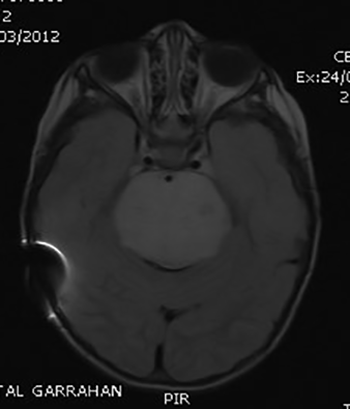

Figura 1:

IRMN T1. Paciente con derivación ventrículo peritoneal por hidrocefalia (nótese el artificio en la imagen) con posterior diagnóstico de lesión difusa de protuberancia al año del procedimiento. Dada la discrepancia entre el tiempo de evolución de la hidrocefalia y el momento de diagnóstico del tumor fue necesaria la biopsia.